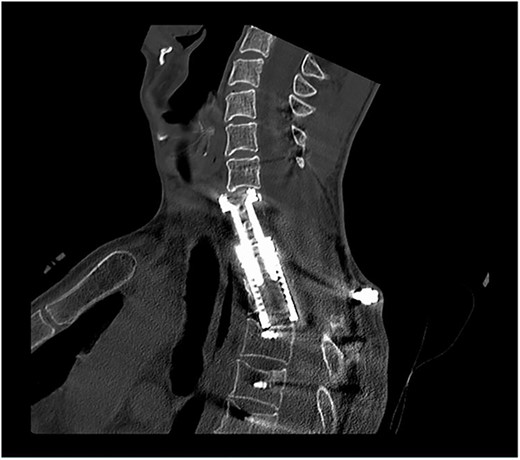

The surgical procedure was completed 5 days later without any complication by decompression of the exiting nerve roots of the first to third thoracic vertebra followed by consequently vertebral resection. After the placement of the distractable vertebral cage, the patient was shifted into the prone position. Then, the fifth cervical to the sixth thoracic vertebra was visualized and further dorsal tumor debulking with removal of the intraspinal mass was performed. Thereafter, lateral mass screws were inserted in C5 and C6. The vertebrae C7, Th4-6 were instrumented using pedicle screws. The rod system was implanted with additive cross-connector insertion (Figs 4 and 5). During the further postoperative course, skin and muscle tissue thinned out, leading to the transfer of a mucocutaneus latissimus dorsi flap over the screws by plastic surgeons 7 months later. Unfortunately, 1 year after the spine surgery, CT scans identified a local tumor recurrence involving C1 to Th6 with the infiltration of the spinal canal and chest wall in the CTJ. The patient suffered from pain in the right shoulder and a paresis of the right hand, which worsened to a mild paresis of the arm. Palliative chemotherapy with carboplatin and etoposide was initiated. The patient died 1 month later because of the further NSCLC progression.

Postoperative sagittal CT scans with 3D-reconstruction after 360° fusion. The vertebral body replacement with a distractable cage, which is displaced anteriorly because of a slight endplate sintering.